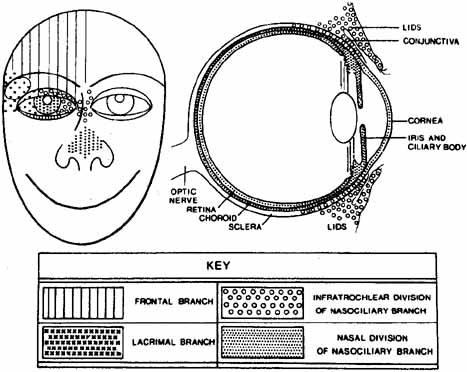

the globe itself is not inflamed.7 The ophthalmic division of the trigeminal nerve has three parts: the frontal

nerve, the lacrimal nerve, and the nasociliary nerve (Fig. 3). The supraorbital and supratrochlear branches of the frontal nerve

supply the upper lid and forehead and are most often involved in HZO. The

nasociliary nerve provides sensory innervation to the cornea, ciliary

body, iris, and conjunctiva. Its terminal branch is the anterior

ethmoidal nerve, which innervates the sides of the tip of the nose (alae

nasae) via the external nasal nerve.  Fig. 3 Distribution of the major branches of first division of trigeminal nerve (cranial

nerve V). (Courtesy of Pavan-Langston

D Herpes Zoster Ophthalmicus: Int Ophthalmol Clin 10(4): 174, 1975) Fig. 3 Distribution of the major branches of first division of trigeminal nerve (cranial

nerve V). (Courtesy of Pavan-Langston

D Herpes Zoster Ophthalmicus: Int Ophthalmol Clin 10(4): 174, 1975)